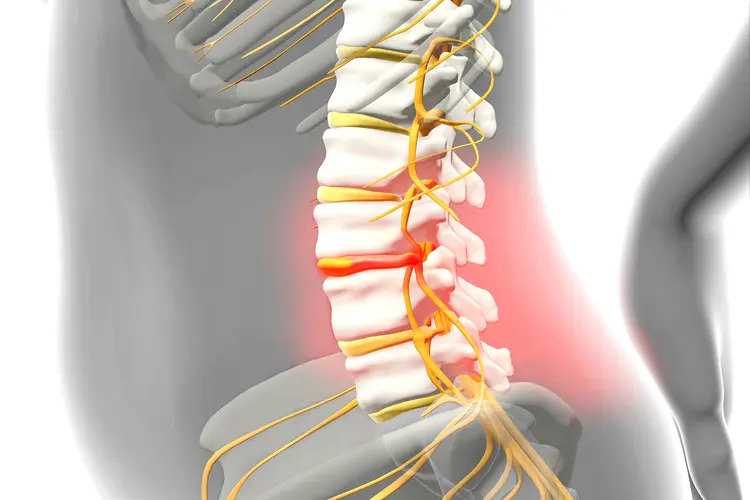

Dr. Italiya has extensive expertise in trauma care, joint replacement surgeries (knee & hip), fracture management, arthritis treatment, and spine-related conditions. His approach focuses on long-term recovery and functional restoration rather than temporary pain relief.